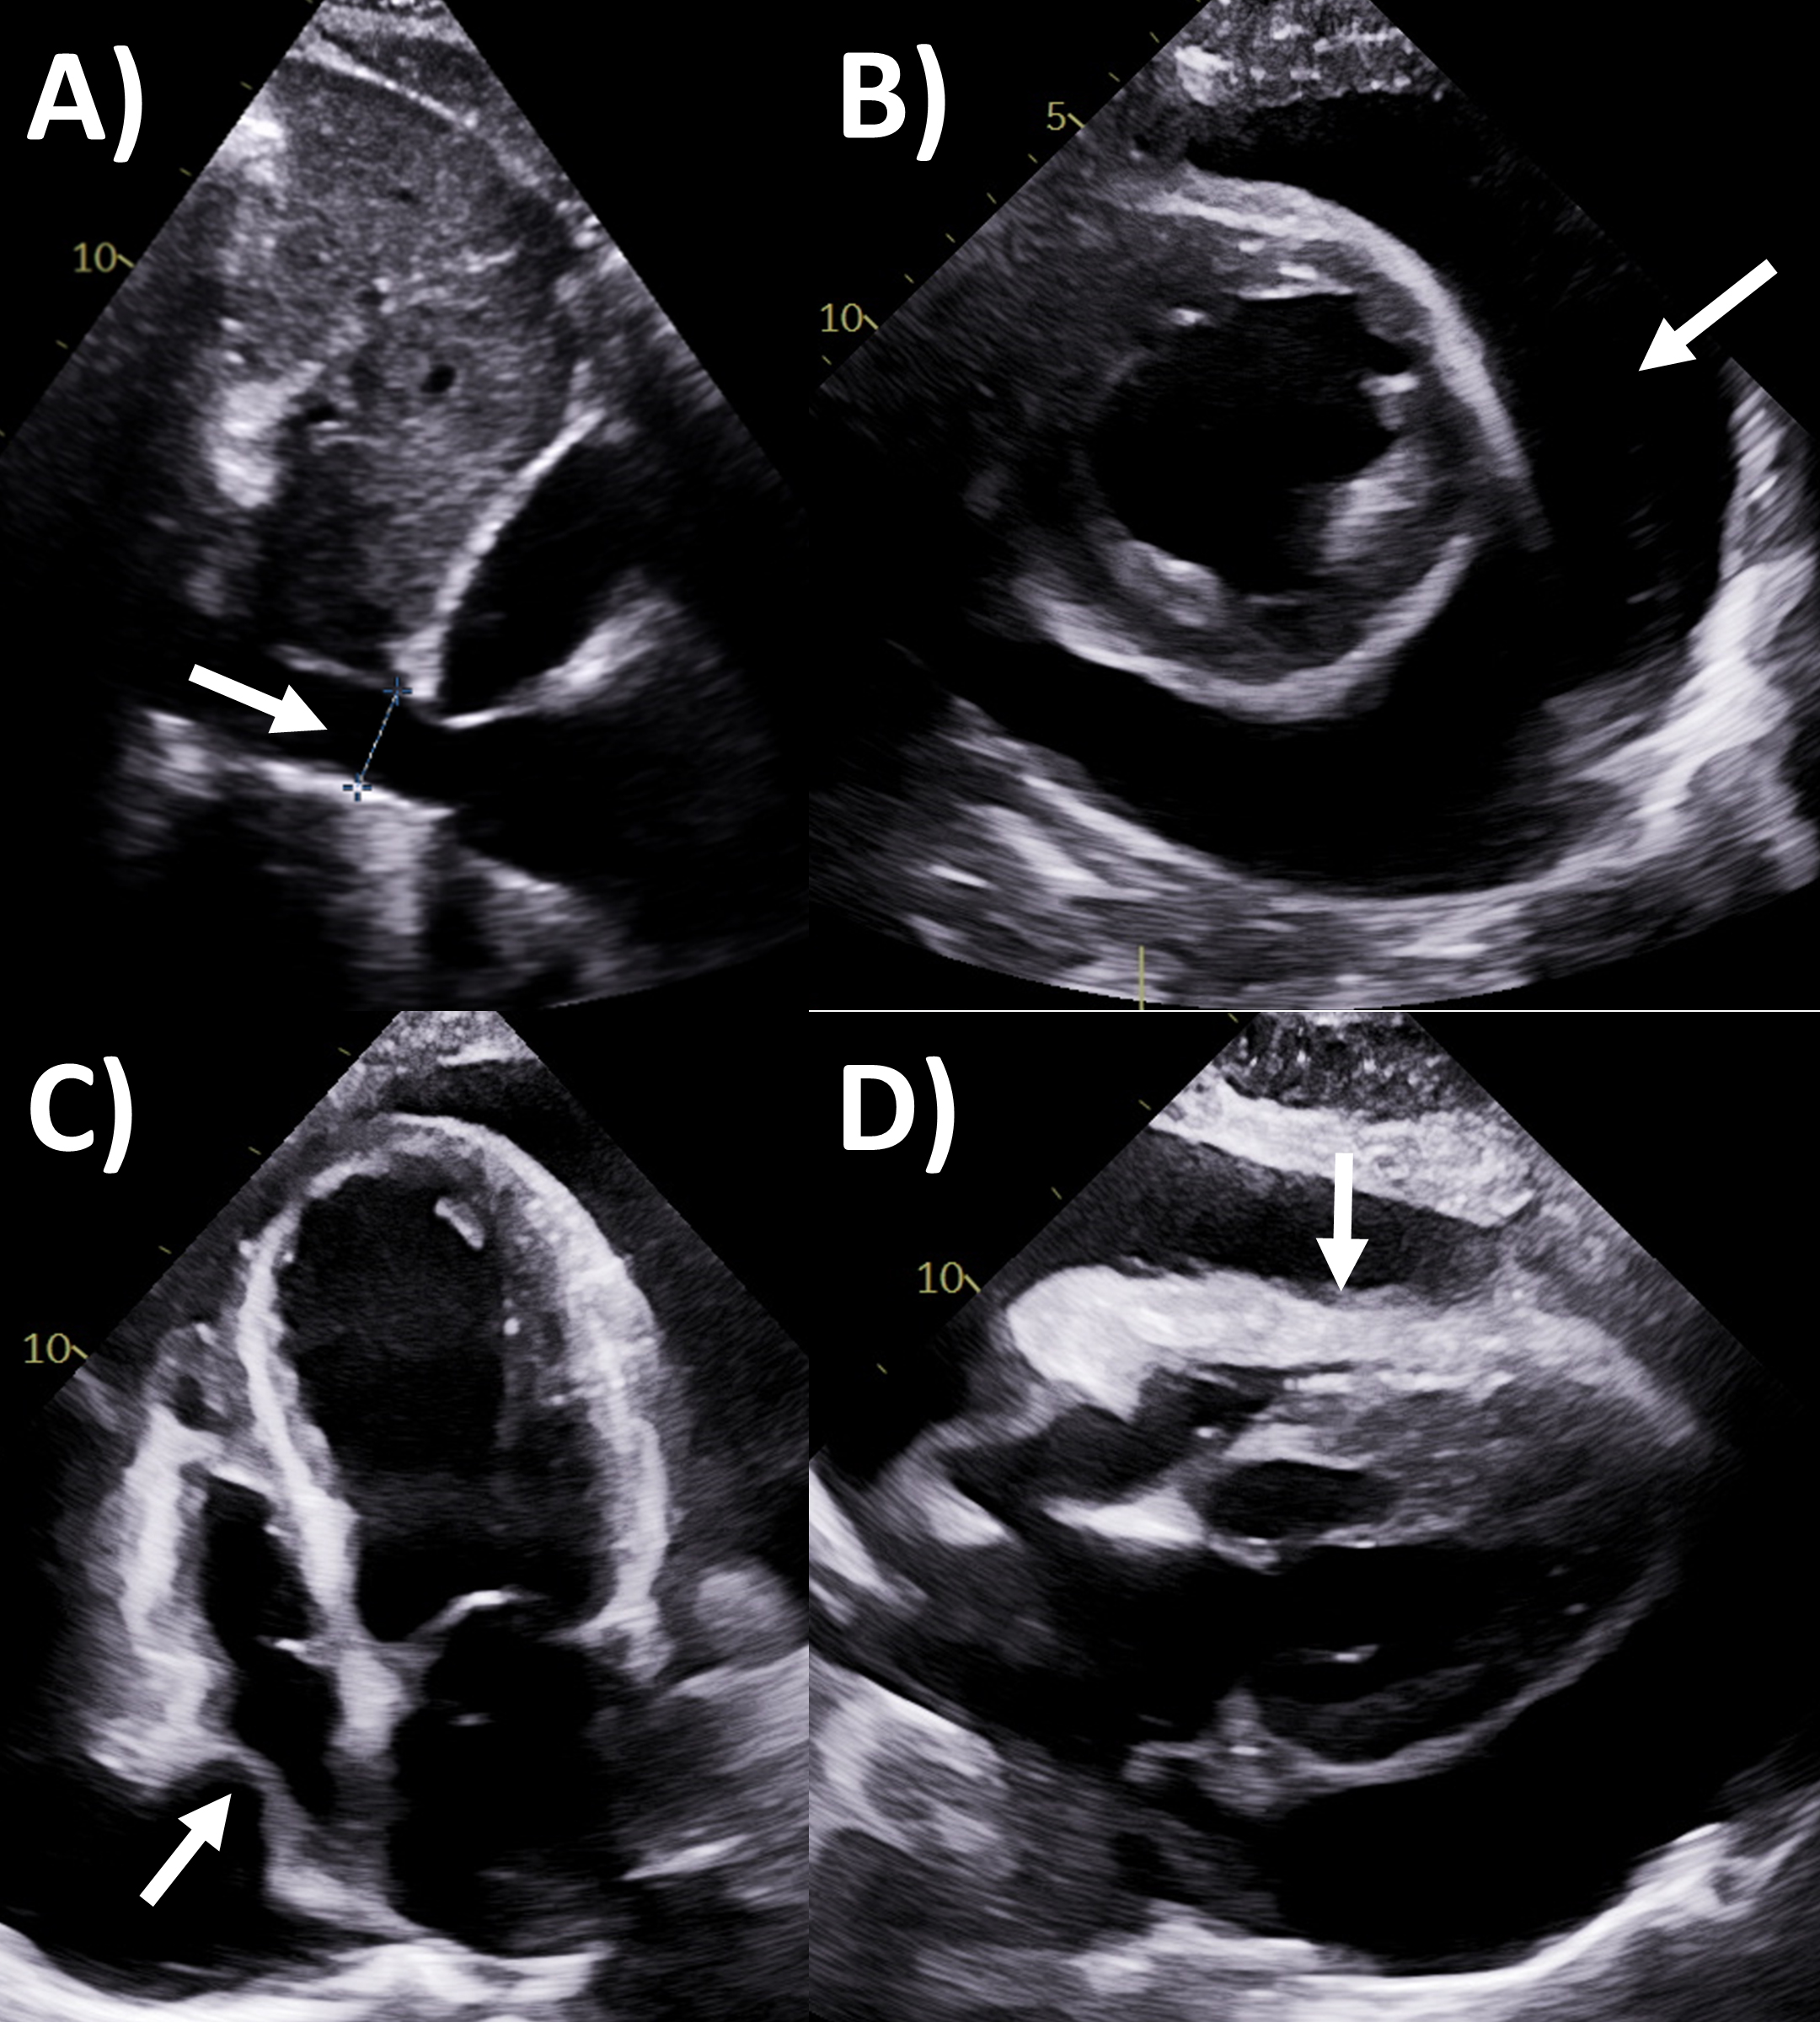

CT has greater ability for tissue characterization than echocardiography, and is able to assess the extent, local or distant spread of masses, lymph node involvement and many pericardial tumors have associated effusions that are hemorrhagic or exudative [31]. Hemangiomas appear heterogenous with contrast enhancement; lymphangiomas are heterogenous with low attenuation and septae; lipoma have low fat-level attenuation that is circumscribed, and sometimes can surround coronary arteries; teratomas usually have contain areas of calcification and fat; lymphoma are hypoattenuating with contrast enhancement; fibromas are homogeneous with no or minimal enhancement given lack of vascularity; sarcomas are broad-based masses which invade adjacent structures; and mesothelioma is seen as diffuse irregular pericardial thickening with effusion [31, 56]. Pericardial cysts are seen as a well-circumscribed homogeneous mass with thin wall on CT, with fluid density, unaffected by intravenous contrast (Fig. 4) [59, 60].

Fig. 4.Multi-modality imaging tissue characterization of pericardial cyst (arrows in all panels) adjacent to the right atrium. (A) Computed tomography axial slice, cyst was 10 Hounsfield units. (B) Magnetic resonance imaging (MRI) steady-state free precession bright blood sequence axial slice, cyst has increased signal. (C) MRI T2-short tau inversion recovery sequence, cyst has high signal. (D) MRI late gadolinium enhancement sequence axial slice, cyst has low signal.

MRI’s main advantage amongst imaging modalities is its ability in tissue characterization, and this is no different when applied to pericardial masses. Depending on tumor extension, the pericardium or myocardium may show thickening, or pericardial effusions, the latter often exudative or hemorrhagic with high signal intensity on T1-weighted sequences [31]. On T1-weighted, T2-weighted and gadolinium enhanced sequences, many tumors have low, high and high signal intensities [14, 31, 61, 62, 63]. Hemangiomas generally appear heterogeneous on all sequences, while lipomas have high signal intensity on all sequences, however its signal can be uniquely suppressed on fat-saturation pulse sequences. Fibroma have low vascularity and therefore have low signal intensity on T2-weighted sequence and none to minimal enhancement on gadolinium enhanced sequences. Mesotheliomas appear homogeneous on T1-weighted but have heterogenenous elevated signal on T2-weighte and gadolinium enhanced sequences. Of note, some studies have suggested heterogenous gadolinium uptake to indicate areas of increased lesion nodularity, growth and/or necrosis [64]. Pericardial cysts also appear as a well-circumscribed homogeneous mass with thin wall on MRI, displaying hypointense signal on T1-weighted sequence unless there is an exudative or hemorrhagic component, with hyperintense signal on T2-weighted sequence and no signal on LGE sequence (Fig. 4) [31, 65]. Lastly, pericardial hematomas show hyperintense, heterogeneous and hypointense signal on T1 and T2 weighted sequences in the acute, subacute and chronic stages, and no signal on LGE sequences regardless of timeframe [31].